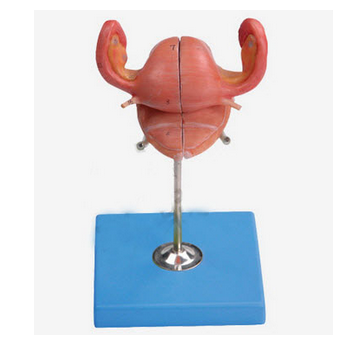

GD/A15108女性內生殖器官模型產品介紹:1、型號規格:GD/A151082、名 稱:女性內生殖器官模型3、品 牌:全科醫生4、簡 介:該模型前面為子宮和陰道冠狀剖面,共有19個部位指示標志...